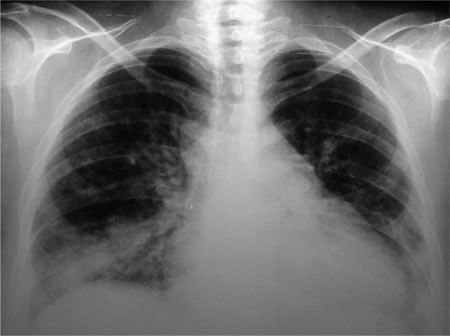

Ciudad de México. Un reciente estudio internacional descubrió que las mujeres que regularmente usan productos de limpieza, en especial aquellos que funcionan como productos profesionales, pueden con el tiempo sufrir un deterioro más rápido de la función pulmonar que las mujeres que no usan esos productos con regularidad. Aunque el estudio no haya examinado ningún producto específico, vale la pena escoger, dentro de lo posible, productos de limpieza con menos sustancias químicas potencialmente tóxicas o productos alternos como vinagre blanco, bicarbonato de sodio o carbonato de sodio. El Dr. Clayton Cowl, Medicina Preventiva, Ocupacional y Aeroespacial de Mayo Clinic aconseja que mantenga bien ventilada el área y nunca mezcle los productos de limpieza.